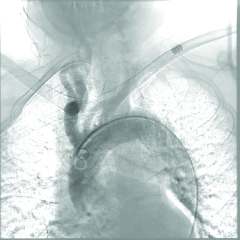

The team proceeded with ultrasound-guided right common femoral artery access. The patient had a Type 3 aortic arch, which made advancement of the catheter difficult due to a sharp angle (Figure 3). Therefore, a curved sheath technique was used with 6-Fr vascular sheath. The Cook 90 cm Shuttle Sheath was manually curved by the operator and then positioned in the right common carotid artery. This was followed by crossing the stenosis using a 0.014 Whisper wire. Eventually, a Medtronic Protege 8–6 × 40 mm carotid self-expanding stent was placed at the site of the lesion in the internal carotid artery after placing the SpiderFX embolic protection device, since other filters were unpassable, which significantly reduced the risk of emboli (Figure 4). After the procedure, the patient was transferred to the CICU in stable hemodynamic condition. Post-operatively, he developed bradycardia without hypotension transiently requiring chronotropic support with a dopamine infusion, from which he was successfully weaned off in a day. Reflexive bradycardia is a well described post-procedural phenomenon following internal carotid artery stenting.

Figure 4

Figure 4. Carotid Artery Angiogram after Stenting. Stent placement increased blood flow slightly and significantly decreased the risk of emboli.